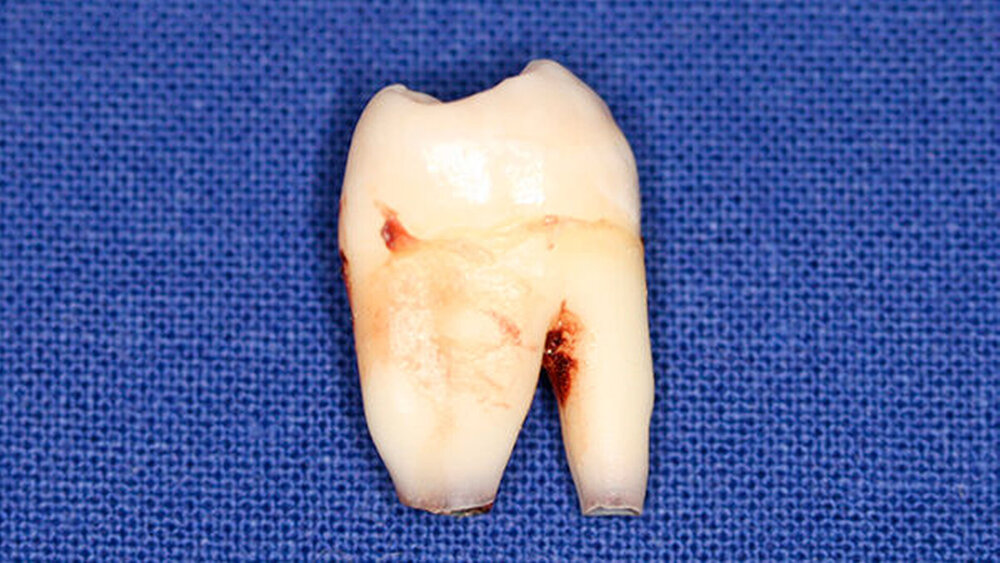

Postoperativ wurden die Zähne in bukko-lingualer Richtung mittels einer diamantbelegten Trennscheibe geteilt. Visuell zeigte sich nun ein großer Hohlraum im koronalen Dentinbereich, sowohl an Zahn 27 als auch an Zahn 47. Die histologische Untersuchung der Zahnfragmente ergab für beide Zähne: Zahnanlagengewebe mit akuter Entzündung (Abbildungen 4 bis 6). Der Patient befindet sich seitdem im regelmäßigen Abstand von sechs Monaten in einem prophylaktischen Recall. Die Abbildung 7 zeigt das postoperative Zahnschema vom 19. August 2015

Der vorliegende Fall zeigt eindrucksvoll verschiedene Stadien der präeruptiven koronalen Resorption (PIR): eine präeruptiv im Röntgenbild sichtbare Transluzenzzone im Dentin des Zahns 47 an der koronalen Schmelz-Dentin Grenze mit intaktem Schmelzmantel und eine große Kavitätenbildung nach Durchbruch des Zahns 27 in die Mundhöhle.

Bei der histologischen Untersuchung der extrahierten Zähne 27 und 47 unseres Patienten wurden Zahnanlagengewebe und Entzündungszellen gefunden. Im Rahmen anderer Untersuchungen konnten resorptive Zellen wie Osteoklasten und Makrophagen an den Rändern der Läsion nachgewiesen werden [Spierer, 2014].